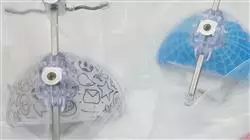

Se trata de un completo Problemas del Crecimiento Transversal y Cómo Tratarlos en el que se mostrará al alumno las dos formas esenciales de tratamiento en este tipo de problemas transversales, como son la disyunción maxilar que consiste en la separación de la sutura media palatina y el tratamiento de expansión dentoalveolar, cuando el problema transversal no sea tan severo. Además, también se enseñarán los tipos de aparatos que existen y cuál es el ideal para cada tipo de paciente.

1.6. Tipos de disyuntores

1.7. Relación con clases III (mentonera y mascara)